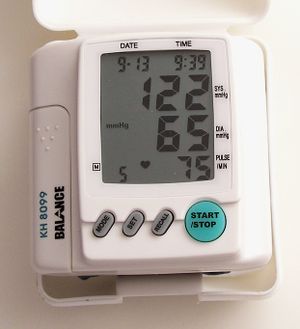

أجهزة قياس ضغط الدم

أجهزة قياس ضغط الدم الحديثة وبخاصة الإلكترونية تقوم بالعادة بقياس النبض إلى جانب قياسها ضغط الدم، حيث يظهر مقدار معدل النبض كرقم ثالث يلي قيمتي الضغط الانقياضي والانبساطي. مثال ذلك 120/60 مليمتر زئبق و80 في الدقيقة، حيث 80 هو معدل النبض في هذا المثال يعني 80 دقة قلب في الدقيقة الواحدة. كثير من هذه الأجهزة تعطي إشارة صوتية لكل نبضة أثناء القياس، وذلك لتعطي فرصة في تقدير كون النبض منتظماً أو غير منتظم.